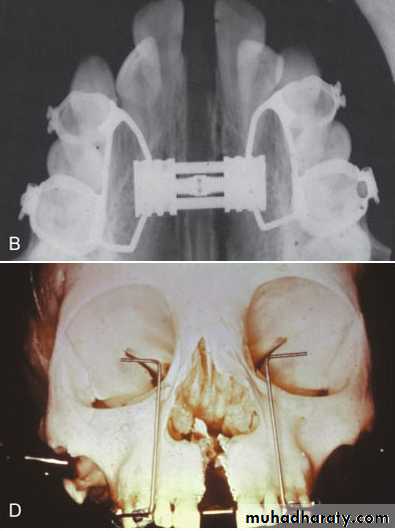

• Implant supported expansionForce can be directly applied to maxilla using palatal screws for attachment of expansion device.

Slow expansion is used since the effect is mainly skeletal.

Surgically assisted rapid palatal expansion

In this procedure the surgeon make bone cuts similar to Le Fort I osteotomy except the down fracture to reduce resistance, followed by expansion with rigid screw to separate halves of maxilla.

Correction of Narrow Maxilla in Adults

Surgical widening of maxilla is the least stable of orthodontic surgical procedures because of the pull of stretched palatal tissues that cause relapse.

Overcorrection of crossbite followed by retention for at least one year after surgery is recommended